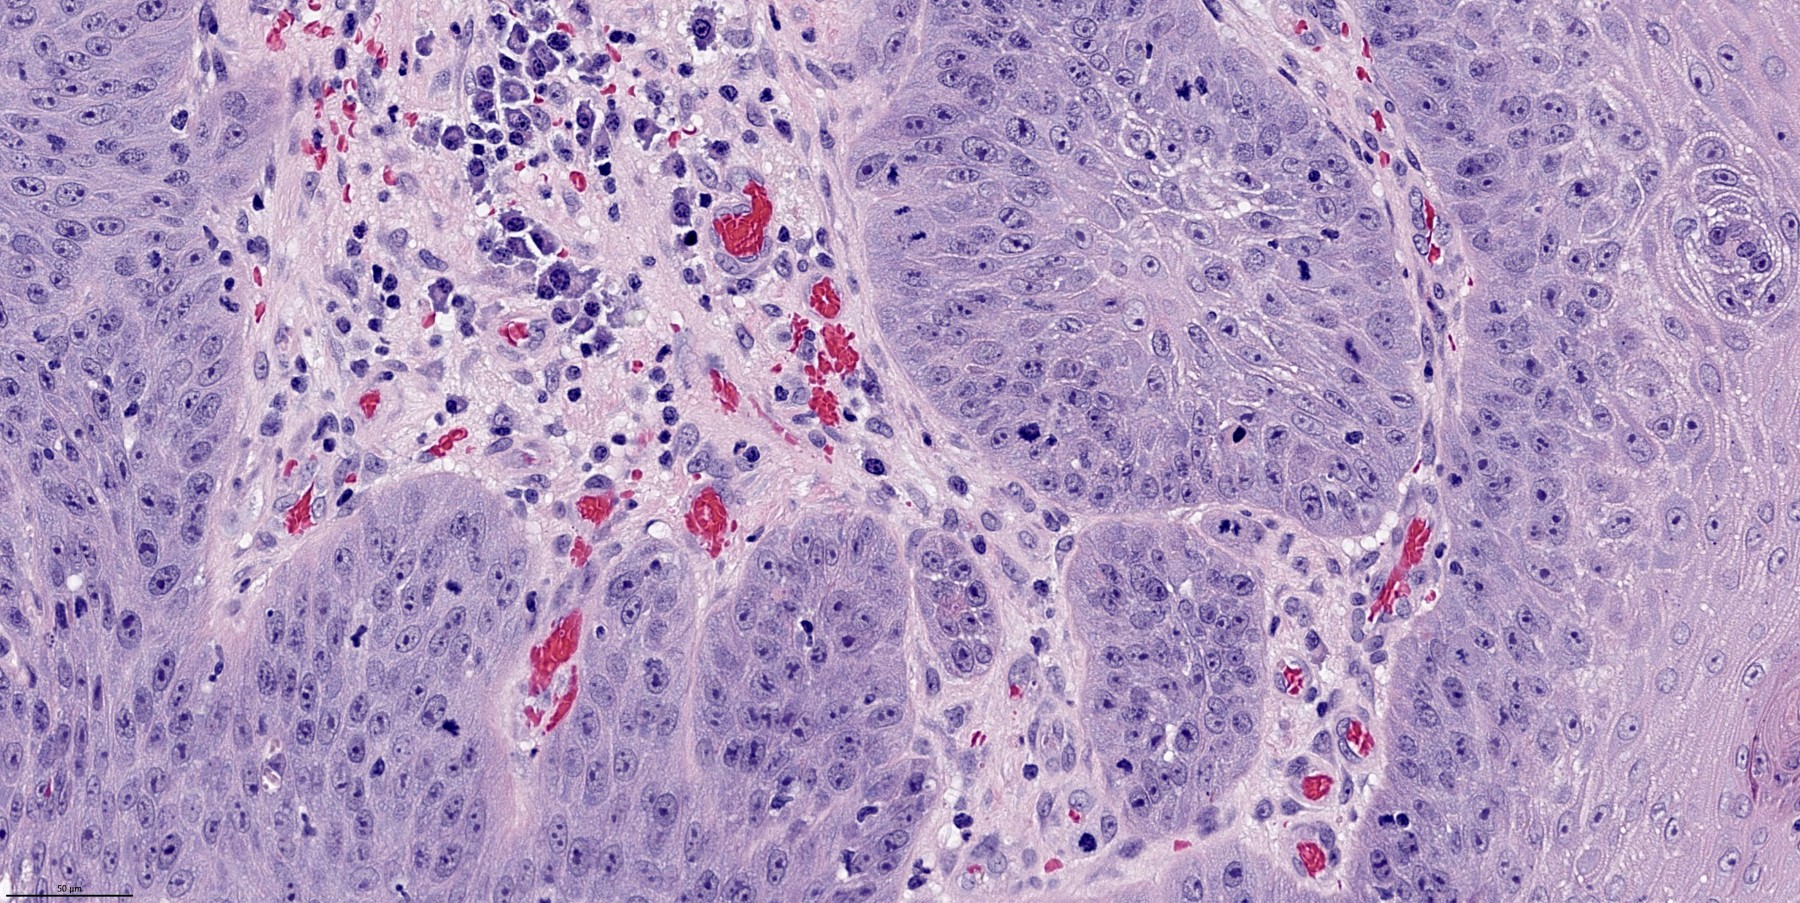

Microscopic (histologic) description

- Finger-like projections or multiple fronds with a central fibrovascular core, covered by benign hyperplastic stratified squamous epithelium

- Basal and parabasal hyperplasia

- Increased mitotic figures in the basal and parabasal layers

- Koilocytic changes in upper layer: may be pronounced or subtle

- Surface keratinization: absent to minimal

- Malignant transformation is characterized by aberrant (paradoxical) keratinization, marked cytological atypia, focal necrosis, increased mitoses and atypical mitoses not limited to the basal and parabasal layers, as well as invasive growth pattern (Respir Med 2017;126:116)

Microscopic (histologic) images